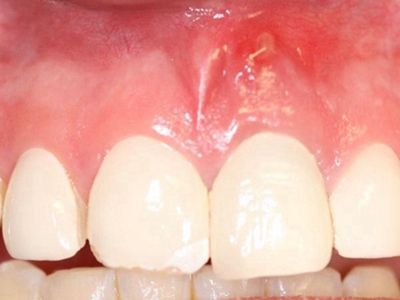

牙龈炎是发生于牙龈组织的炎症,患者可出现牙龈出血伴肿胀、发红、正常形态改变和偶尔不适等症状。本病主要由口腔卫生状况差导致,包括口腔不洁、牙菌斑等,诊断依据临床检查,治疗包括专业牙齿清洁和加强家庭口腔卫生。

牙龈炎可先引起牙齿与牙龈之间的沟(龈沟)加深,然后牙龈充血,炎症围绕一个或多个牙齿,伴牙龈乳头肿胀和易出血。一般无痛,可自行消退,也可维持轻度炎症数年。